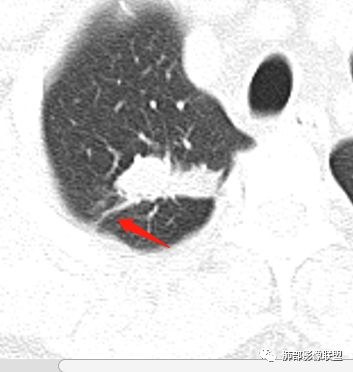

病史:男性,49岁,反复咳嗽月余,伴左胸痛;   影像:形态奇特,长毛刺,疑多灶,支气管阻塞不明显,毛刺不明显,纵膈窗密度不均,其内似见低密度,有凹陷,膨隆不除外,纵膈窗胸膜有点增厚。诊断:结核(右上肺)鉴别:不符合,无钙化,无胸腔积液;腺癌(无淋巴结)。处置:寻找结核相关检查,肿标,纤支镜,增强。

患者中年男性,主诉:咳嗽  胸痛。  胸CT:右肺上叶尖段占位,病灶位于支气管外,病灶周围部分区域可见毛玻璃影,病灶边缘不规则,部分区域可见平直,胸膜牵拉(无胸膜凹陷),柔软长毛刺,分叶,纵隔窗病灶没可见低密度区,左肺尖可见一点状病灶,病灶整体考虑良性疾病:感染性病变(结核?),感染后机化?。恶性病变待除外。

右肺上叶结节,边缘平直为主,病灶比较散,周周似乎有卫星病灶,边缘有胸膜牵拉,从粗到细,左肺尖奕有卫星灶,综合考虑结核。

晨读:患者中年男性,反复咳嗽1月余,伴左胸部疼痛1周就诊。胸部CT:右肺上叶尖后段不规则结节,见长毛刺、胸膜牵拉、条索影,周围见卫星灶。未见明显淋巴结肿大,符合结核病变。鉴别其他。但其病灶位于右肺,主诉左胸痛,是误写,还是?

一米阳光:    晨读,右上肺结节影,形态不规则,边缘平直,部分凹陷,长软毛刺,胸膜牵拉,周围卫星灶。考虑结核。鉴别腺癌,部分边缘彭隆

傅昌瑜:  男,49岁,反复咳嗽1月余,伴左侧胸痛1周。右肺上叶尖段结节,边缘平直、凹陷,周周似乎有卫星病灶,边缘有胸膜牵拉,从粗到细,左肺尖见小点状病灶,考虑良性病变,结核可能性大。

小飞:  晨读:右肺上叶不规则结节灶,沿支气管走形分布,边缘平直,U型凹陷,脊柱侧有少许磨玻璃影,左肺尖少许斑点灶,综合考虑结核。

南边:这病史,慢性或亚急性炎症,癌都可以

影像,气管憩室,两肺尖都有病灶,长索条

右肺上叶病灶两部分

纵隔窗提示内侧部分密度不够实

边缘平直、凹陷为主,部分膨隆

内部小点状影提示可能支气管腔内粘液栓

左肺尖及右肺病灶附近见小斑点,边界尚清

1、病灶整体形态不是类圆形,边缘凹陷、平直为主,长轴重建可能更明显,长索条,附近卫星灶,左肺尖有类似小高密度影;按常规:首先要考虑结核

结果:结核合并真菌(曲霉菌)感染